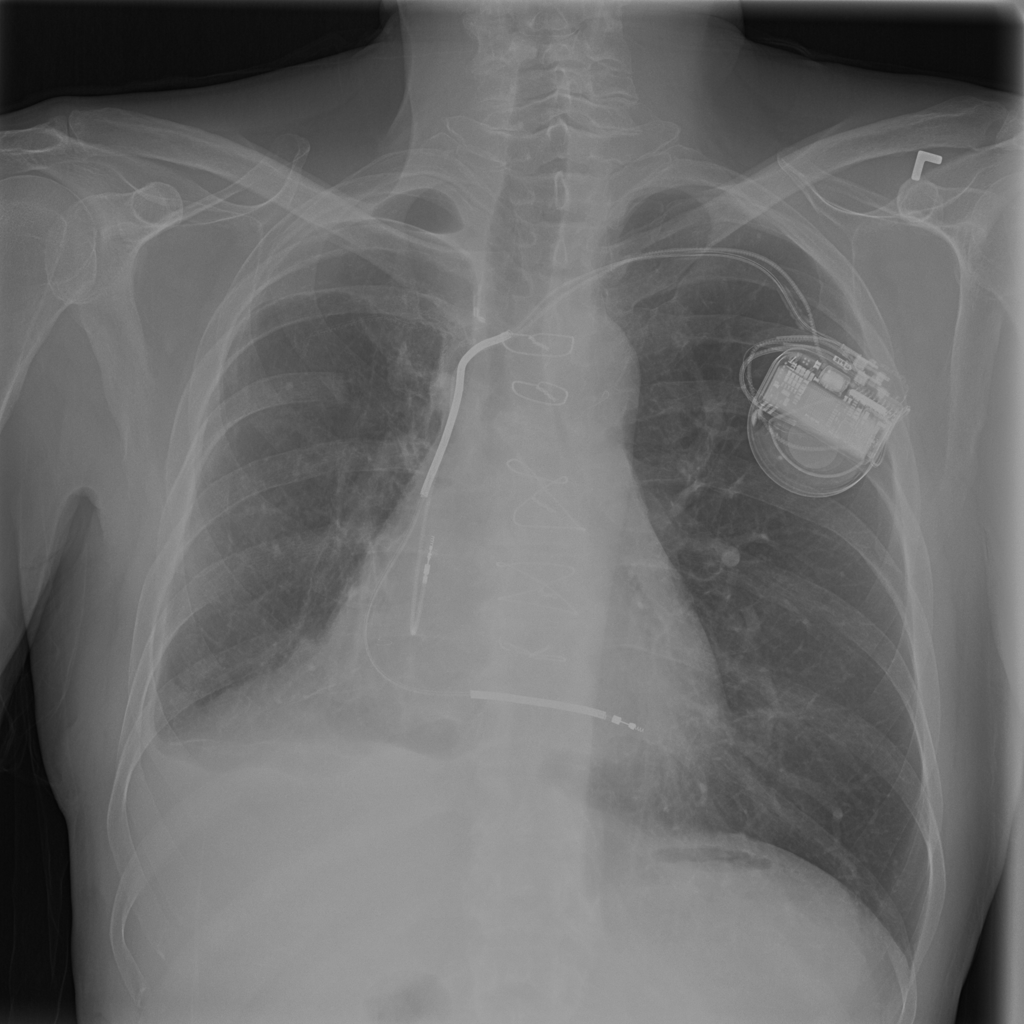

Pneumothorax

Pneumothorax means air is present outside the lung in the pleural space, which can allow part of the lung to collapse. It is an important imaging finding because the size and clinical impact can vary widely.

Showing up to 90 reference images for Pneumothorax.

PAT-50E5 · IMG-001Pneumothorax

PAT-50E5 · IMG-001

AP